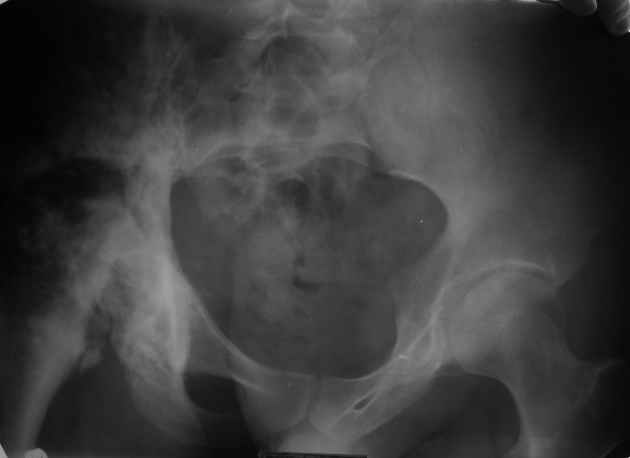

Ангиосаркома таза, тазобедренного сустава

Уважаемые коллеги! Парень 28 лет, болен ангиосаркомой в течении 12 лет.

Лечился радио-, химиотерапией. На сегодня конечность неопорная, болевой синдром. Жизнь проходит в постельном режиме, лечение направлено на её продление. В головных и региональных клиниках России расценивают ситуацию, как достойную лишь консервативного паллиатива. Возможно ли в такой ситуации лечение, кроме радио- и химиотерапии, хотя бы улучшающее качество жизни? Чем могут помочь зарубежные клиники?

Dear colleagues! The guy of 28 years, is sick with angiosarcoma of pelvis during 12 years. He was treated with radio-, chemotherapy. For today there are limb not basic, a painful syndrome. Life passes in a bed, treatment is directed on its prolongation. In head and regional clinics of Russia regard a situation, as worthy only for conservative palliative treatment. Is it possible treatment, except for radio and the chemotherapy, improving quality of life in such situation? Can foreign hospitals offer the help?